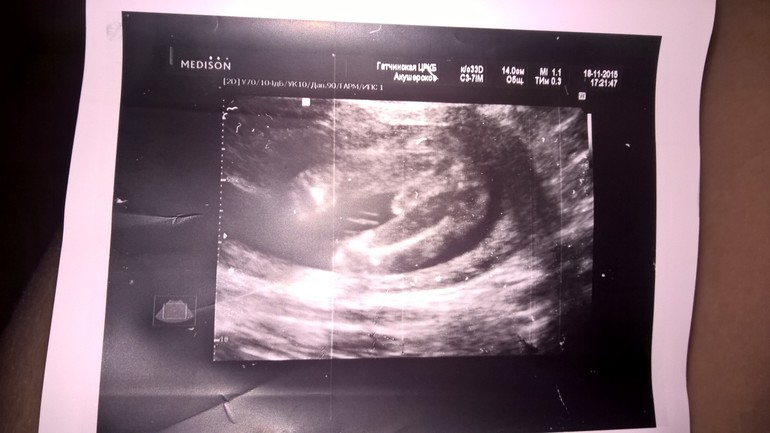

Результаты: УЗИ, КТГ, доплера, скринингаВчера на акушерском сроке 19нед и 4дня прошли второй скриниг😊 С нами был наш папочка, весь испереживался, дышал через раз, все заусенки на пальцах пообрывал😄😄😄 Теперь о главном: С малышом, тттфу, все отлично, развивается как надо, только чуть опережает события😊и по узи нам уже 20нед и 4дня😊 лежит зайчик мой головкой вниз, пинает мамку ооочень активно😃 правда головка у нас оочень низко, доктор сказал… даже решил посмотреть вагинальным датчиком все ли нормально с шейкой, но там тоже ттфу, все Ок, шейка длинная, закрытая. Но меня беспокоит такое расположение головки, потому-что давит и спина побаливает и слева спереди в области яичника. Плюс ходить тяжело, в области лобка чувствую распирание и покалывает иногда очень сильно, сначала думала с кишечником беда и он там так раздулся, но нет, со стулом все ок! Врач все проверил, сказал что все норм, но из-за чего это и надо ли себя в чем-то ограничивать(например пастельный режим) не сказал, много народу было… К вам девочки вопрос, у кого такое было на таком сроке, что вам говорил и советовал врач? А так все у нас отлично, мой мальчик 355гр весит😍 и я попросила доктора показать нам с папой достоинство нашего мальчика, чтоб убедиться, что в 16 недель не ошиблись. Когда мы увидели яйки и петуна нашего сыночка, обалдели и обомлели😊 у нас просто богатырь, все девки наши будут😊 там такооое достоинство, что точно не перепутаешь😄😄😄